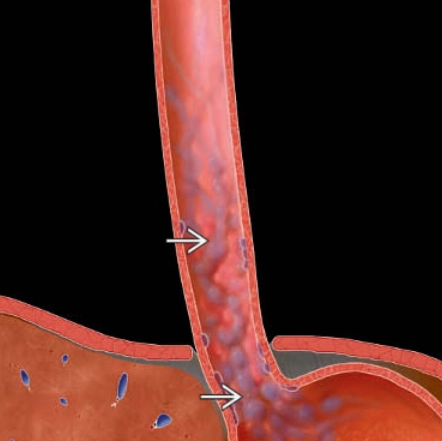

• Giãn tĩnh mạch thực quản

• Giãn tĩnh mạch thực quản (Esophageal varices)